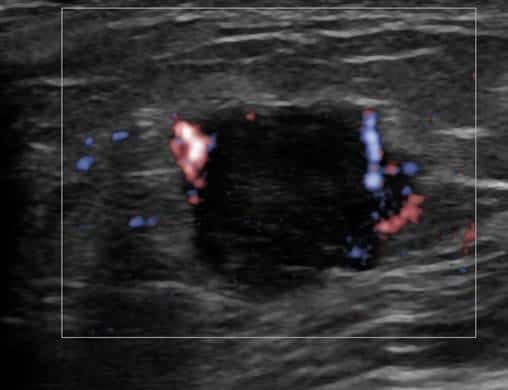

Ung thư vú

Ung thư vú - Ảnh 2

Ung thư vú - Ảnh 3

Ung thư vú - Ảnh 4

» Thông tin: Nữ giới – 55 tuổi.

» Lâm sàng: Khối tuyến vú.